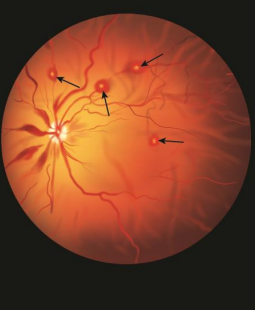

What are Roth spots?

Pale-centered retinal hemorrhages seen in some cases of endocarditis.

What is the significance of Roth spots in infective endocarditis?

They represent a minor criterion and are immunologic phenomena resulting from immune complex deposition.